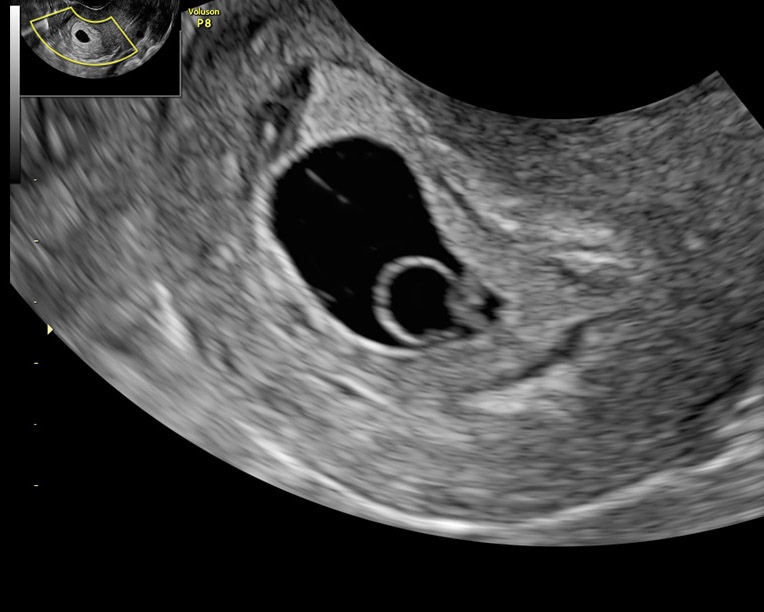

УЗИ-аппарат VOLUSON P8 от компании GE относится к среднему классу медицинского оборудования и является идеальным выбором для небольших клиник, отделений и диагностических кабинетов. GE продолжает подтверждать свое лидерство на рынке, предлагая высокотехнологичные решения по разумной цене.

Данный сканер, Voluson P8, заслужил прекрасную репутацию не только в России, но и во всем мире. Он успешно продается и применяется в течение многих лет без дополнительного обслуживания. Врачи по всему миру довольны его надежностью и качеством работы.

Voluson P8 открывает широкие возможности для диагностики не только в коммерческой медицине, но и в других областях. Этот сканер позволяет расширить спектр медицинских услуг и открыть новые направления в диагностике.

Преимущества аппарата Voluson P8 в области акушерства и гинекологии включают:

• Простота проведения обследований: Аппарат Voluson P8 предоставляет простоту использования при проведении обследований в акушерстве и гинекологии. Независимо от телосложения пациента и плотности кожной ткани, оборудование обеспечивает высокую точность диагнозов.

• Акушерство и гинекология: Voluson P8 обеспечивает высокую точность диагностики беременности, оценку развития плода, обследование матки и яичников, а также другие акушерские и гинекологические исследования.